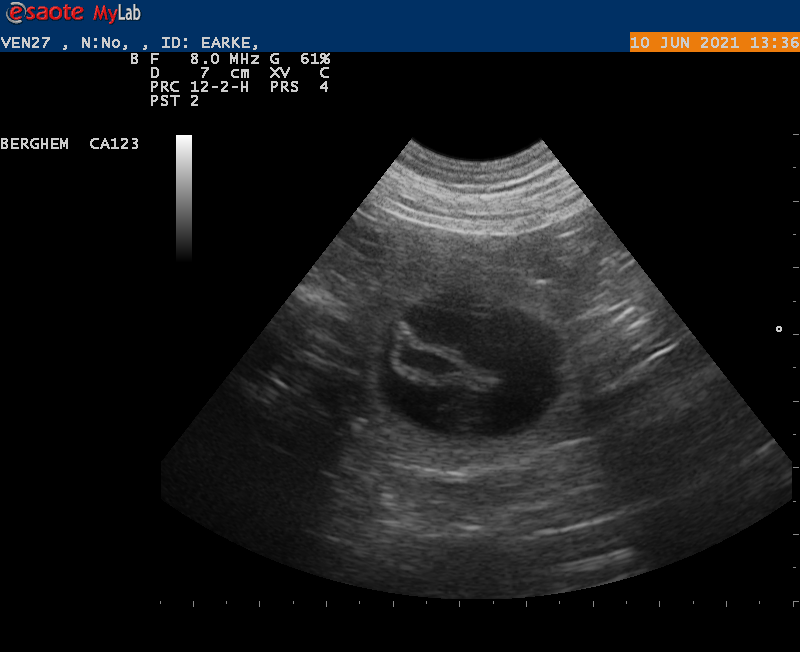

Goed nieuws!

10-6-2021

Vanmiddag zijn we naar de dierenarts geweest met Earke voor een echo. Super goed nieuws: Earke is drachtig. We hebben zelfs al de hartjes zien kloppen van de pups.

Als alles goed blijft gaan krijgen we rond 14 juli een nestje van Earke en Douwe.